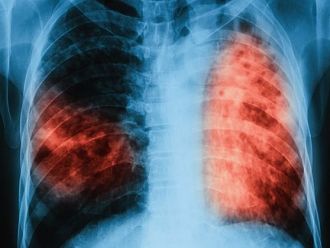

В България през последните години се наблюдава тенденция на намаляване на заболеваемостта от туберкулоза - от 39.1 на 100 000 през 2006 г. до 18.5 на 100 000 през 2019 г. Това показват данните от Националната програма за превенция и контрол на туберкулозата в България за периода 2021-2025 година.

През 2019 г. са регистрирани 1344 пациенти с туберкулоза, като за сравнение през 2018 г. те са били 1358, а през 2017 г. - 1463, което показва тенденцията на намаляване на броя на случаите с туберкулоза. Броят на регистрираните случаи на туберкулоза, респективно и заболеваемостта, варира значително по региони, като в някои региони в северозападна и централна България заболеваемостта е над средната за страната.